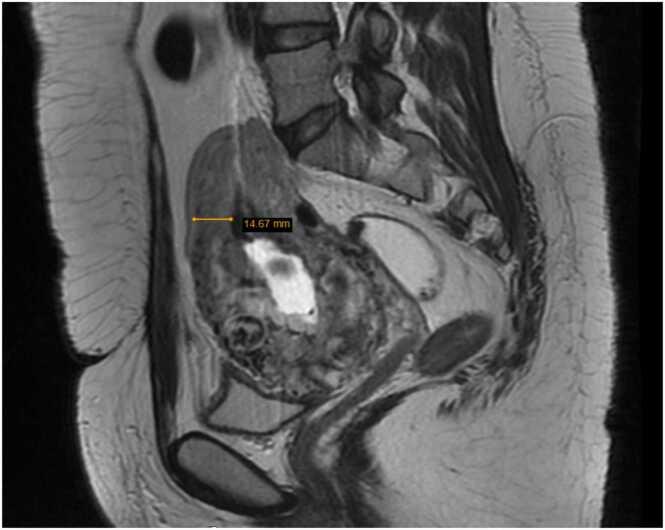

Cesarean Scar Pregnancy (CSP) is defined as an ectopic pregnancy in which the gestational sac implants on the surgical scar of a previous cesarean section or isthmocele.Despite its low incidence, the diagnosis presents a significant difficulty, and a false negative diagnosis can lead to serious complications that may require more aggressive treatments.

Cesarean Scar Pregnancy (CSP) should be considered among the diagnostic options when finding a gestational sac located in atypical situations in patients with a history of cesarean section.Early diagnosis and treatment are crucial for achieving the best outcomes. A minimally invasive approach should be planned as first-line treatment in all situations where CSP is included in the differential diagnosis.

剖宫产瘢痕妊娠(CSP)被定义为一种异位妊娠,即妊娠囊着床于既往剖宫产手术瘢痕或子宫峡部憩室处。尽管其发病率较低,但诊断存在显著困难,假阴性诊断可能导致严重并发症,可能需要更积极的治疗。

当在有剖宫产史的患者中发现妊娠囊位于非典型位置时,应将剖宫产瘢痕妊娠(CSP)纳入诊断选项之中。早期诊断和治疗对于取得最佳结果至关重要。在所有将CSP纳入鉴别诊断的情况下,应计划采用微创方法作为一线治疗。